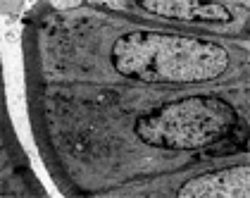

Immunregulation der Epithelzellbarriere im Darm

Mitochondriale Regulation im Darmepithel

Epithelialer Metabolismus bei Infektion und Entzündung im Darm